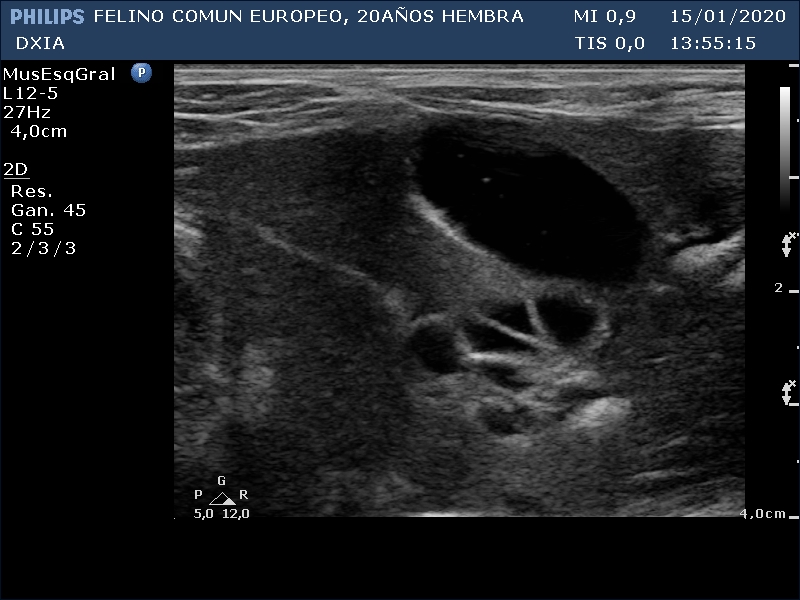

FRANGELICA

Se realiza ecografía y se observa alteración compatible con neoformación en asa del intestino delgado.

Asa del ID con aumento de grosor de su pared, pérdida de estructura en capas. Neoformación hipoecogénica.

Ganglio yeyunal con aspecto globoso, hipoecogénico y bastante homogéneo, índice mayor de 0.5. Compatible con mayor probabilidad con proceso tumoral o metastásico.

Asa del ID con neoformación sin definición de capas intestinales.